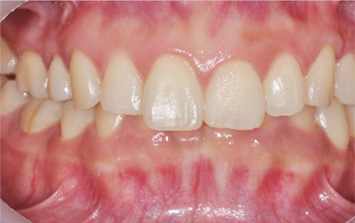

윗니가 아랫니를 과도하게 덮고 있는 과개교합 환자분. 과개교합의 경우 윗니가 아랫니에 가해지는 힘과 압력이 있어 턱 관절 및

근육 손상이 되기 때문에 반드시 교정치료가 필요합니다. 환자분의 경우도 아래 앞니 윗면이 닳아 있고 치아가 시린 상태. 클리피씨와 미니

스크류를 이용하여 위 치열 후방이동 하는 교정을 진행하였습니다.

위 치열 후방이동으로 앞니의 치아 물림이 개선되었고, 앞니의 시림 증상도 사라졌습니다. 과개교합의 경우 환자 스스로 눈치 채지 못하는 경우가 많고,

사각 턱 안모가 동반되는 경우가 많기 때문에 꼭 정밀 검사를 받아보는 것이 좋습니다.